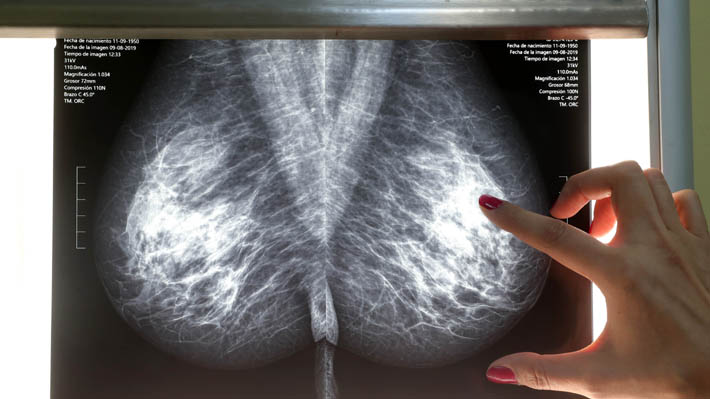

Estos hallazgos sugieren el potencial de estos compuestos bioactivos para el desarrollo de nuevos agentes terapéuticos contra el cáncer de mama, “una de las enfermedades más comunes y mortales en mujeres en todo el mundo y que, a pesar de los avances en el diagnóstico y tratamiento, sigue siendo difícil de tratar y con una alta tasa de mortalidad”, señala el comunicado. Es más, según la Organización Mundial de la Salud (OMS), esta enfermedad representa el 16% de todos los cánceres en pacientes mujeres.

Cabe recordar que en el mes de octubre se conmemora la lucha contra el cáncer de mamas “con el fin de sensibilizar y generar conciencia para que las mujeres puedan acceder a un diagnóstico y tratamiento oportuno, haciendo énfasis en las estrategias de detección precoz”, señala la web de la Red de Centros de Salud Familiar de la facultad de Medicina de la Universidad Católica.